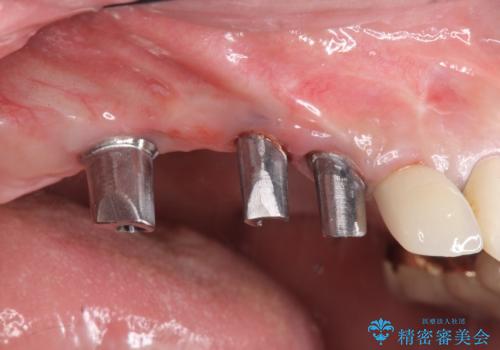

- 他院で1本インプラントを入れたまま治療に通うことができなくなり、途中からの治療を希望され来院されました。

既に埋入されているインプラントは位置が悪いのでそのまま骨内に留置することとし、新たに咬合機能を回復すべく3本のインプラントを埋入すると同時に吸収した骨幅を増やし、安定してインプラントで噛める環境整備を目指します。

インプラントが長持ちするために、インプラント周囲の十分な骨量・角化歯肉の存在・安定した咬合を一つづつ整備する治療を行いました。